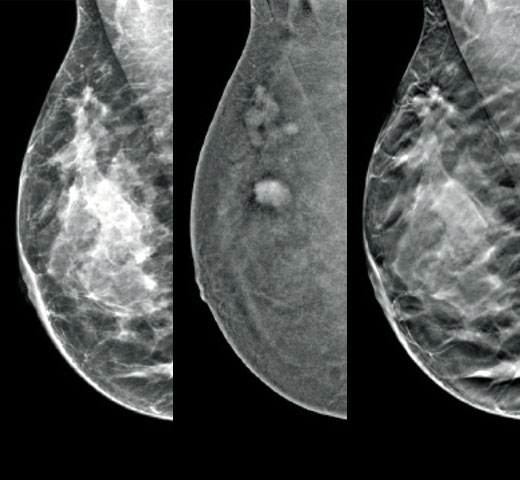

Higher breast density is known to increase a woman’s risk for breast cancer.1 The need for accurate, unbiased analysis is therefore critical. Powered by machine learning, Quantra technology software analyses both 2D™ and tomosynthesis images for distribution and texture of parenchymal tissue. It categorises breasts in four breast composition categories consistent with guidance from the American College of Radiology (ACR) BI-RADS Atlas 5th Edition.2

Breast imaging scans